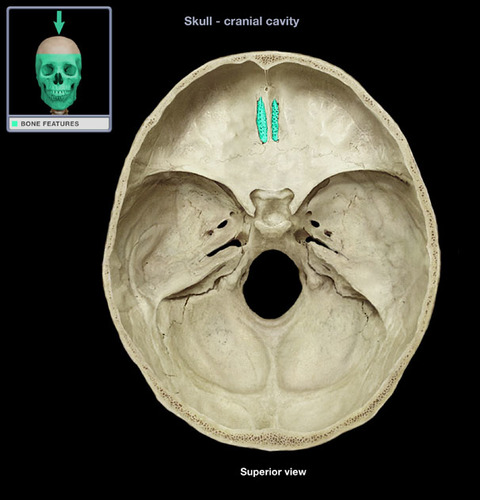

crista galli

cribriform plate